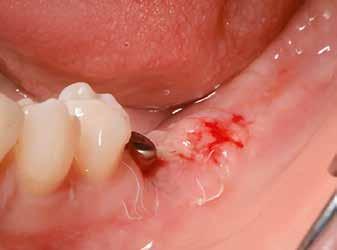

horizontális metszéssel kötöttük össze (2–5. ábra). A metszések hosszát és a köztük lévő távolságot minden esetben a lágyszövet augmentációhoz szükséges keratinizált szövet határozza meg. A lebeny deepitelizációját egy 15C-s szikepengével végeztük (6. ábra). Ezt követően félvastag lebenyt preparáltunk (7. ábra). A lebenyt apikálisan, az alapjáról belső, felületes metszéssel felszabadítottuk, hogy passzívan áthelyezhessük és rögzíthessük, feszülés nélkül. Meziális irányba 180 fokkal átforgattuk (8–9. ábra). A meziális papillát alagúttechnikával (tunnelling technique) készítettük elő a graft befogadására (10. ábra). Az így kialakított lebenyt a recipiens ágyban rögzítettük az újonnan kialakított vesztibulum alapjánál 5-0 nem felszívódó PTFE (Coreflon, IMPLACORE) varratokkal. A graftot behajtottuk az ínyszél alá és meziális oldalon rögzítettük PTFE varratokkal (11–14. ábra) A műtétet követően napi kétszeri, 0,12%-os klórhexidin tartalmú szájvízzel történő öblögetést javasoltunk a páciensnek, két héten keresztül. Gyulladáscsökkentésre 8 óránként 400 mg Ibuprofént javasoltunk, három napon keresztül. A páciens elmondása szerint sem fájdalmat, sem különösebb diszkomfortot nem tapasztalt. Ezt követően, további 4 héten keresztül, 0,2%-os klórhexidin tartalmú szájvízzel történő öblögetést javasoltunk a betegnek és instruáltuk, hogy lehetőleg ne mossa fogkefével az érintett területet. A varratokat egy héttel később távolítottuk el. A donor és a recipiens terület – 10 nappal a műtétet követően – kiválóan gyógyult (15–16. ábra). Az ezt követő kontrollokat a következő időpontokban ejtettük meg: kettő, illetve négy héttel a műtét után, majd három, hat és tizenkét hónappal később, ezt követően pedig félévente (17–20. ábra). Minden kontroll alkalmával professzionális fenntartó kezelést végeztünk a területen.

11. ábra: A Kígyó lebeny (varratok disztális részén).

12. ábra: A graftot a meziális oldalon rögzítettük PTFE varrattal.

13. ábra: A graft az ínyszél alá húzva.

14. ábra: Közvetlenül a műtét utáni kép, az utolsó öltések lenyomják a lebenyt, hogy ne maradjon szabad terület.